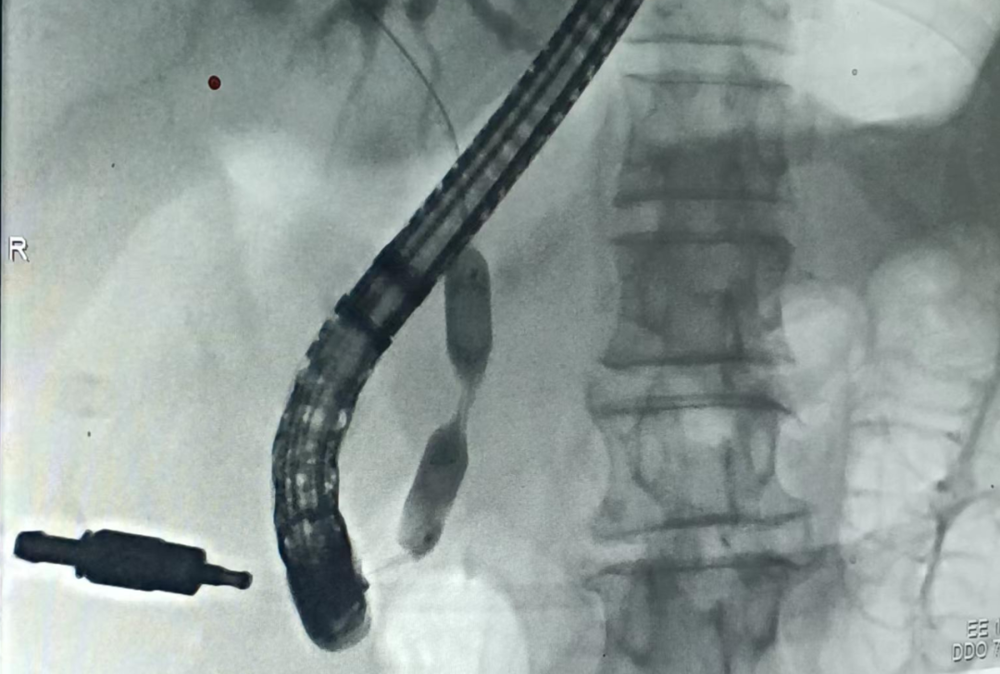

ERCP術目前不單純僅僅運用於膽胰疾病的診斷(duàn),主要運用於(yú)膽胰疾病的(de)治療(liáo)。在消(xiāo)內鏡操作領(lǐng)域ERCP被稱為“皇(huáng)冠上的明珠(zhū)”,不僅因其宏觀理論複雜,且其細微技巧(qiǎo)方(fāng)麵內容也極其繁多。ERCP在膽道狹窄的診斷及治療過程中,都(dōu)發揮非常重要的作用,手術創傷小,並發症少,不僅可以行膽道狹窄(zhǎi)部的刷檢及病理組織活檢,更主要的是通過狹窄部位的擴張及(jí)支架的置入可以很快的緩解患者的症狀。2023年11月15日內三科在上級醫(yī)院專家的指導下(xià)順(shùn)利(lì)完成了一例膽道(dào)狹(xiá)窄(zhǎi)支(zhī)架置入術,緩解患者多年來一直(zhí)在外地往返(fǎn)就醫的困擾。

病例資料(liào):患者,周(zhōu)某某,男,51歲。反複尿(niào)黃、眼黃6年餘,6年前在上級醫院診斷為自身免(miǎn)疫(yì)性胰腺炎並膽管狹窄,間斷給予強的鬆治療後症狀反複,2023年11月13日查肝功能(néng)示(shì):直接膽紅素:35.7umol,11月15日行膽(dǎn)道狹(xiá)窄支架置入術(shù),11月20日複查(chá)肝功能示(shì):直接膽紅素:14.11umol,療效明確。

柱狀球囊擴張示狹窄部位